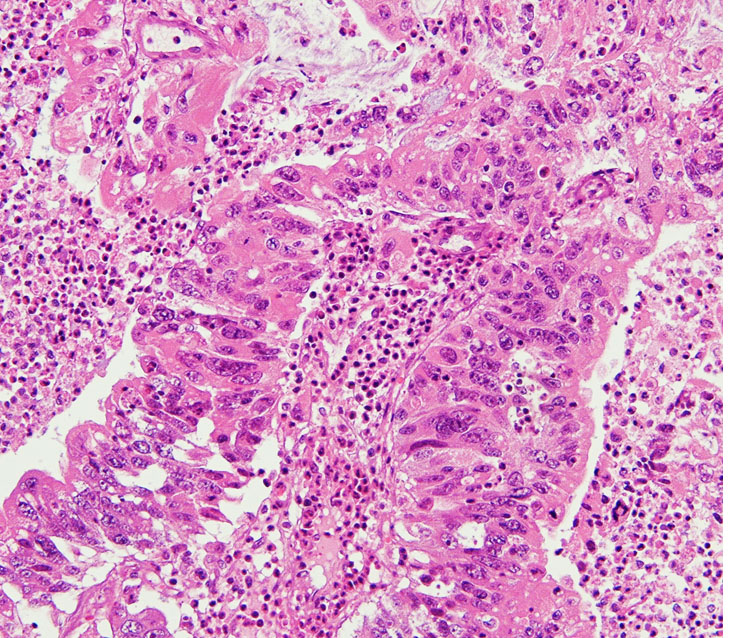

転移性脳腫瘍の手術と病理診断の意義

転移性脳腫瘍の摘出標本です。粘液産生もあり中分化型管状腺癌 tublar adenocarcinomaと診断されます。おそらく大腸癌からの転移ということは予想できますが,正確な臓器が解るわけではありません。かつては,病理診断をするために転移性脳腫瘍を生検することなどもありましたが,ペット PETなどの診断方法が発達した近年では,診断のための転移性脳腫瘍の手術がなされることはほとんどありません。